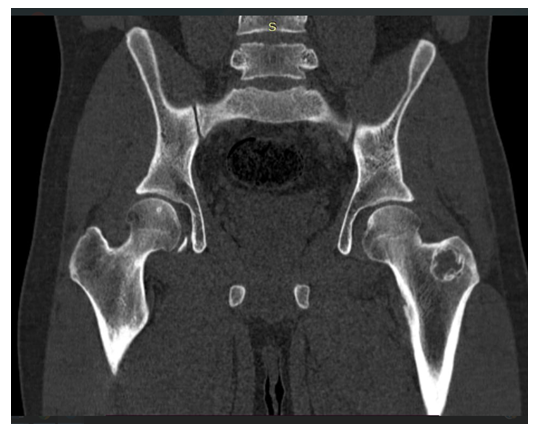

In the patient shown in Figure 3, metastatic involvement of the greater trochanter of the left femur was identified, with less than 50% involvement of the cortical layer, resulting in a low risk of pathological fracture for this patient. | Figure 3. Metastatic involvement of the greater trochanter of the left femur (computed tomography: low risk of pathological fracture, with cortical involvement less than 50%) |